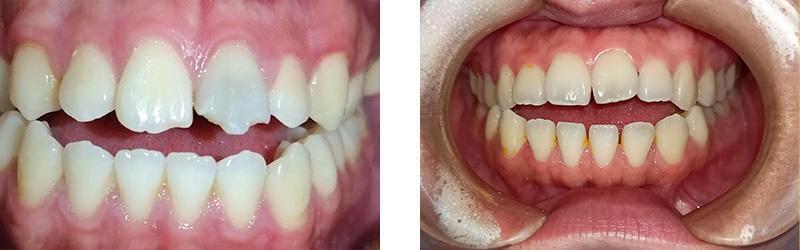

病例分享